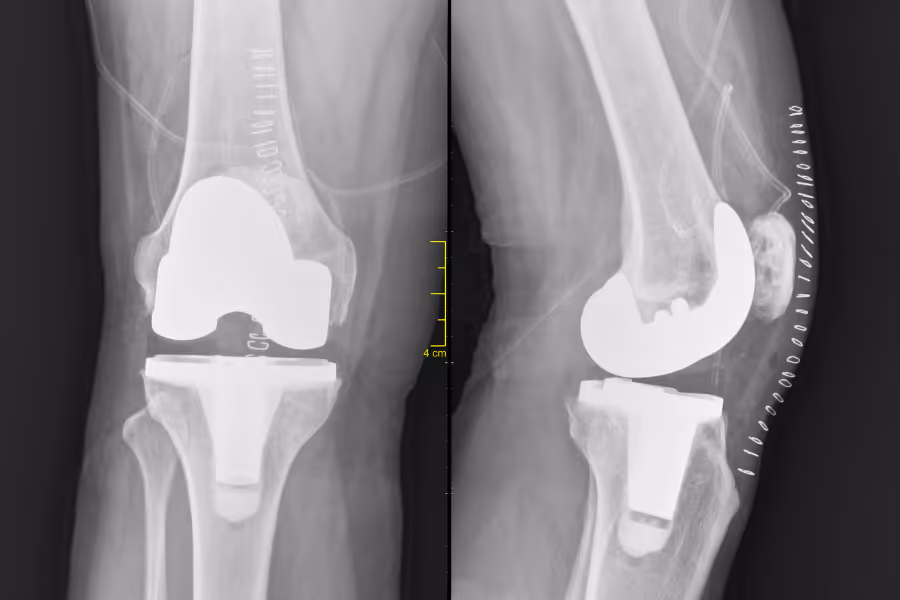

A primary knee replacement is the first time a surgeon replaces the damaged joint surfaces with metal and plastic parts.

A revision knee replacement means you’ve already had a knee replacement, but something has gone wrong or worn out, and the surgeon needs to repair, exchange, or replace some or all of the components.